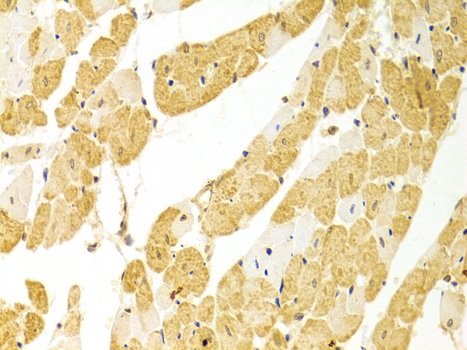

PLCB1

Anti-PLCB1 Polyclonal Antibody